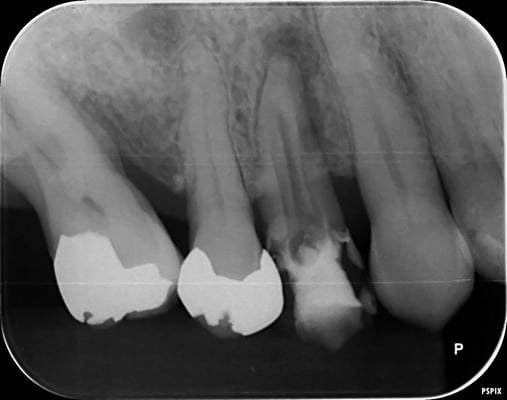

1年後

根尖の透過像も消失し、自覚症状(咬合痛などもありません)安心して最終印象採得(型どり)を行いました。

当院では、CTやレントゲンを撮影して悪い像(根尖などのX線透過像)が消失するのを確認してから補綴するようにしています。

透過像が残っているまま、治療を終了させるアメリカ的な合理主義的な考え方には断固として共感できませんね。